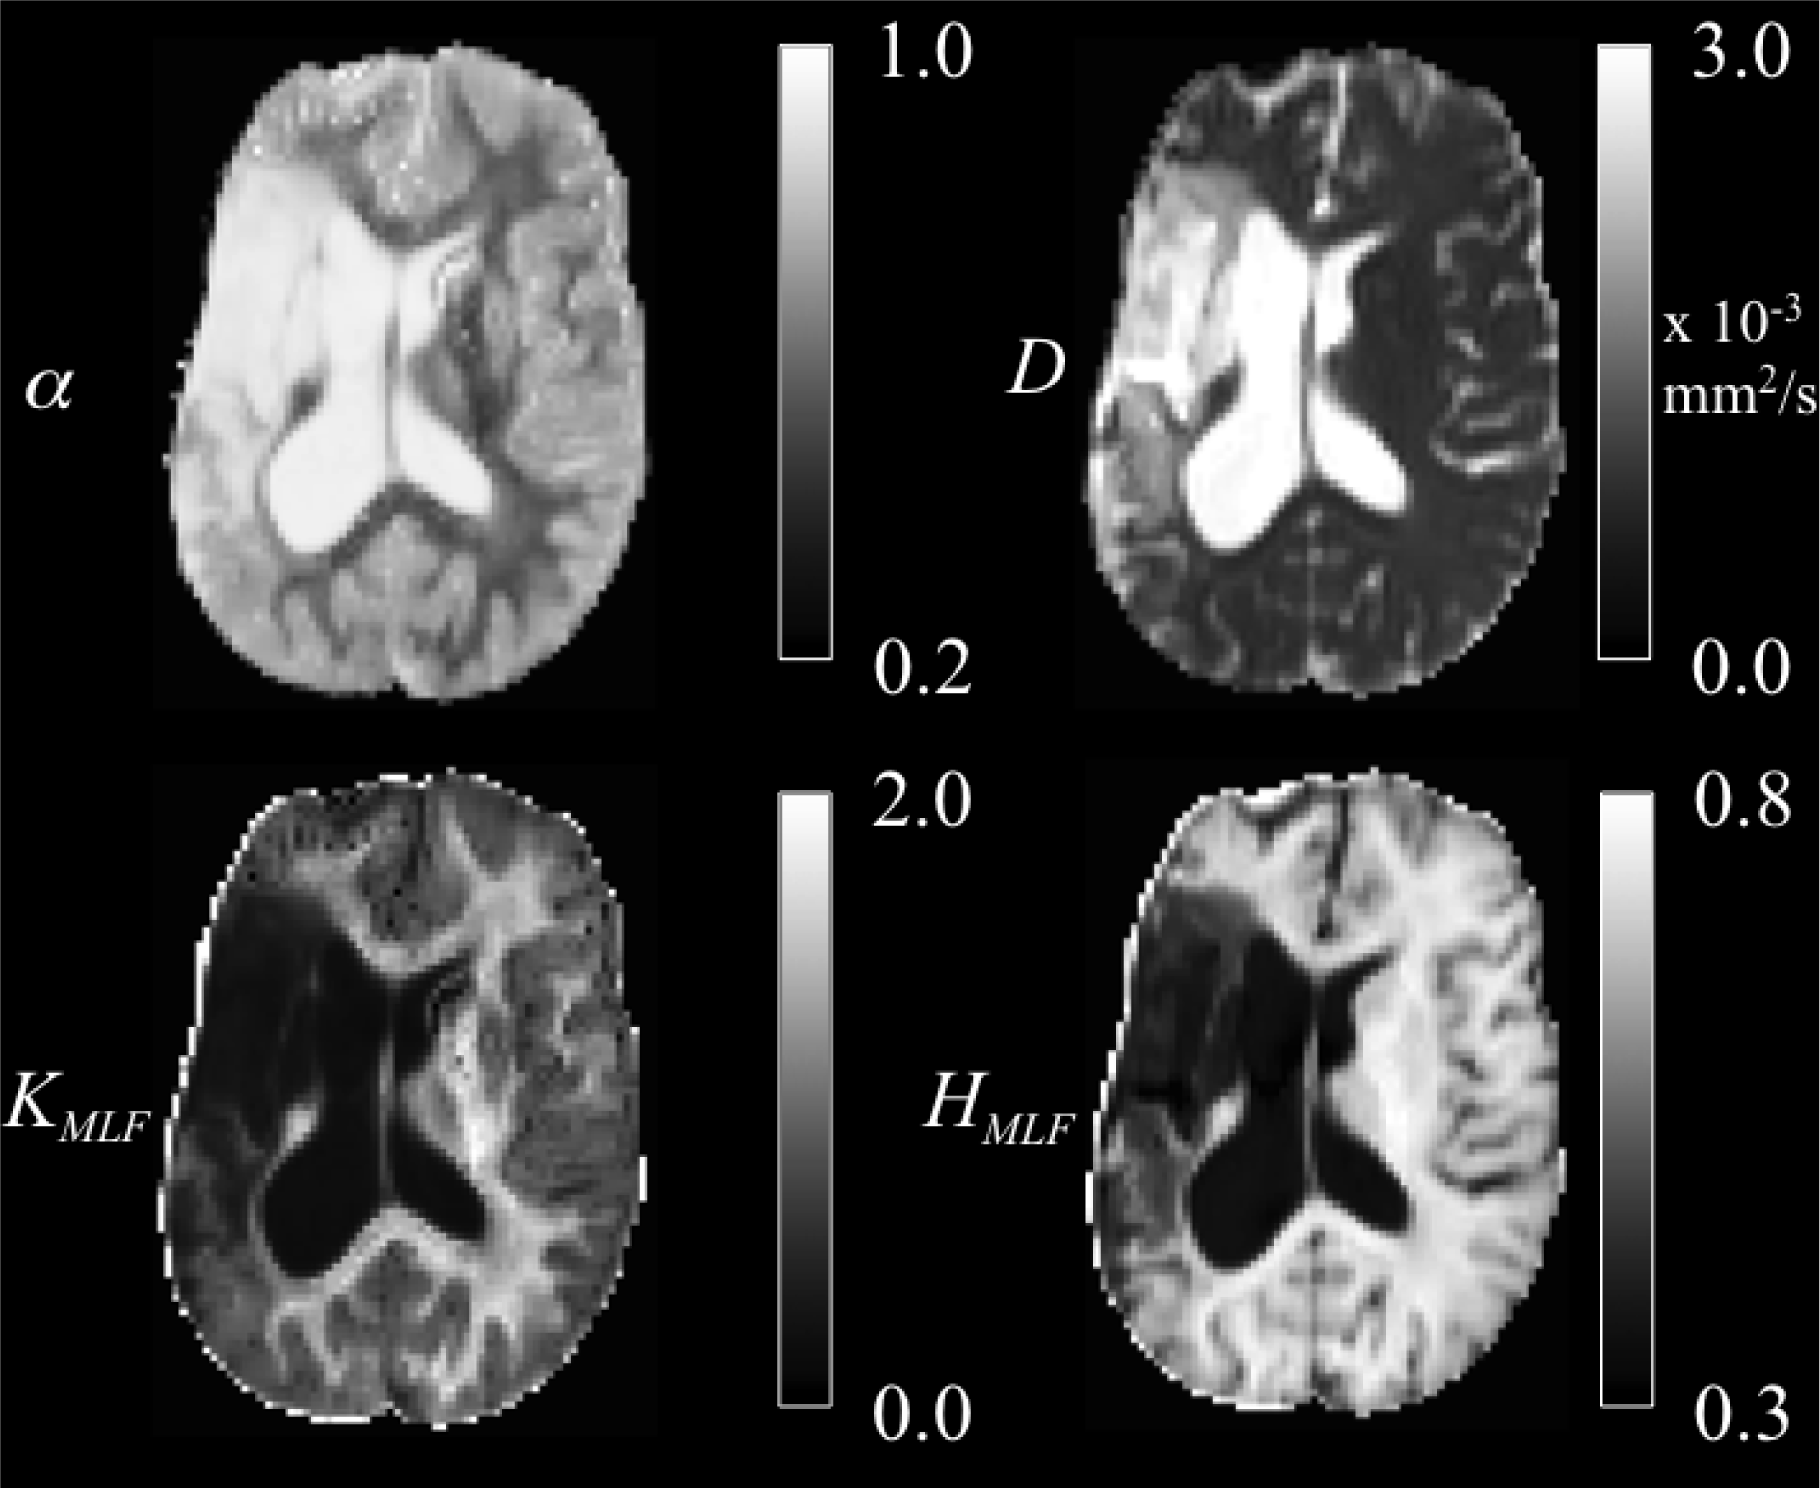

. The Rician noise-corrected diffusion weighted images were skull-stripped utilizing the Brain Extraction Tool [15]. All skull-stripped and Rician noise-corrected diffusion weighted images were co-registered to the b = 0 image space using statistical parametric mapping software (SPM8). Using the Levenberg–Marquardt minimization algorithm in MATLAB (Natick, MA, USA), the average of the three diffusion weighted direction data were fit on a voxel-wise basis to Equation (9) with the MLF algorithm in [16,17]. Following estimations of D and α, the excess kurtosis, KMLF, was computed using the conversion provided in Equation (19). Following estimations of D and α, the CF in Equation (9) for p(k, t) was constructed using N = 100 increments arrayed over variable b-values between 0 and 10 000 s/mm2. Then, the entropy (defined in Equation (22)) in the diffusion process, as modeled by the MLF, was computed as HMLF. The isotropic parameter maps of D, α, KMLF and HMLF for the same axial slice through the stroke patient’s brain are shown in Figure 4.

Figure 4.

Trace parameter maps of α, D, KMLF and HMLF for an axial slice through a brain of a chronic stroke patient.

The ischemic tissue (IT), in the right hemisphere of the patient’s brain (left side of the image), has a diffusion coefficient, D, value (∼ 3 × 10−3 mm2/s), which is similar to the typical value found for the cerebral spinal fluid (CSF) of the ventricles. As can be seen in the contralateral hemisphere, prior to the onset of the stroke, the brain slice would have appeared symmetrical with white matter (WM) and gray matter (GM) voxels. However, as these data were acquired ∼ 2 years following onset, the IT microstructure has degenerated (necrosis), such that the bulk diffusion coefficient has increased to an unhindered value. Furthermore, the diffusion in the IT is close to Gaussian as α ∼ 1, indicating a monoexponential behavior, which is also the case for the CSF. The trace values for D in the healthy WM and GM are ∼ 1/3 of the values in the IT and CSF, with the WM possessing an overall slower diffusion than measured in the GM.

As the scale in the D map in Figure 4 spans 3 × 10−3 mm2/s, the contrast between WM and GM is difficult to discern; however, in the α map, the WM/GM contrast is clearly visible with the WM demonstrating more subdiffusive behavior compared to the GM. The KMLF map also has clearly visible GM/WM contrast and appears as a negative image in the α map, due to the nearly inverse relationship between KMLF and α in Equation (19). The entropy, HMLF, map provides a stable image in which there is visible and smooth GM/WM contrast, with the IT and CSF exhibiting low values of entropy due to the unhindered Gaussian diffusion dynamics. Interestingly, voxels exhibiting low values of α, representing highly subdiffusive dynamics, also have relatively high entropy estimations (particularly in the WM) to indicate a diffusion propagator with a heavy-tailed pdf. In correspondence with entropy, there is high kurtosis estimated for the diffusion propagator pdf in regions of low values of α. However, kurtosis and entropy are not interchangeable measures of the diffusion propagator pdf, evident not only in the images shown in Figure 4, but also mathematically distinct in the forms of Equations (19) and (22). Specifically, in consideration of the CF, α and KMLF are measures of the deviation from a monoexponential form with a rate of the diffusion coefficient, D, whereas entropy considers the entire CF, which includes both the monoexponential component, D, and the non-Gaussian component, α, of the diffusion profile. As kurtosis is defined as the normalized fourth moment in Equation (16), it can be readily seen that the variance, or D, is canceled out when dividing Equation (18) by Equation (13).